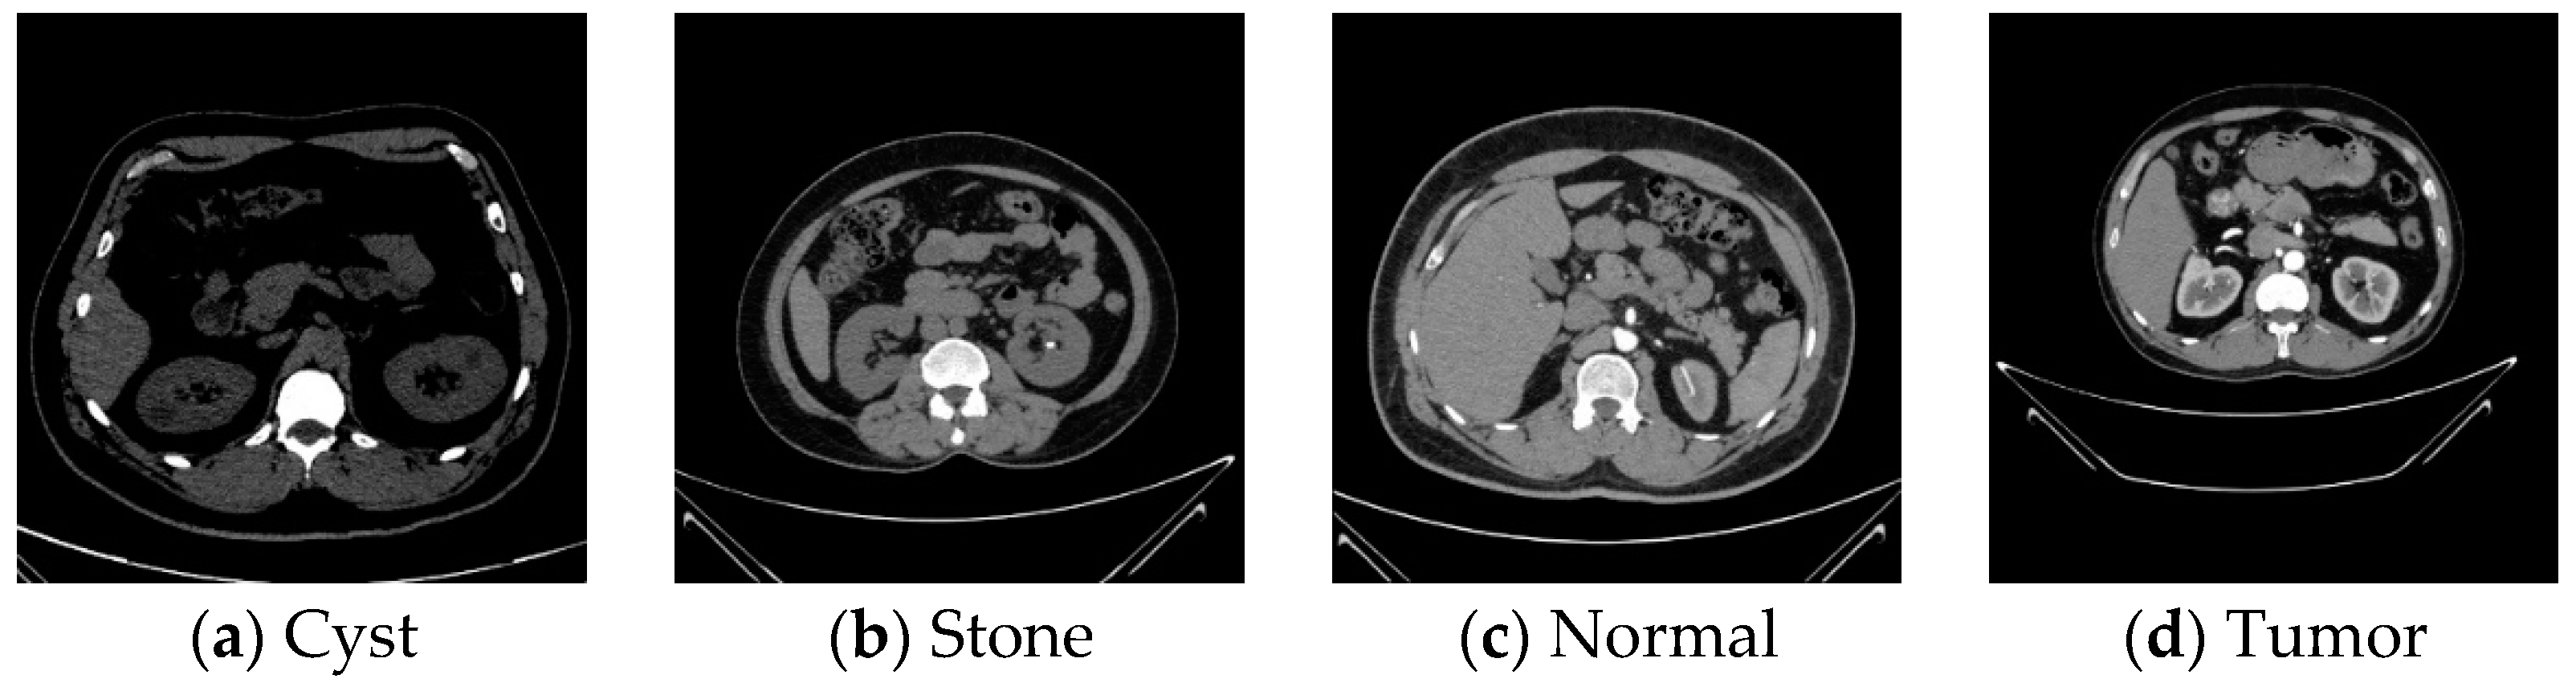

The dataset obtained consists of 12,510 distinct CT images. We selected a subset of 12,400 images, allocating 3709 to cysts, 5031 to normal tissue, 1377 to stones, and 2283 to tumors [40]. Figure 9 shows CT kidney images of normal, cyst, stone, and tumor. Normal kidneys are characterized by a smooth cortex and medulla. Kidney cysts appear on CT images as round or oval-shaped lesions, usually dark in color and with sharp edges. Kidney stones appear as dense masses, usually bright white on CT images. The size and location of the stone determines the severity of symptoms. Kidney tumors may appear different in density from normal kidney tissue. The size, shape, and location of the tumor are also important.

Figure 9. CT examples for cyst, stone, normal, and tumor.